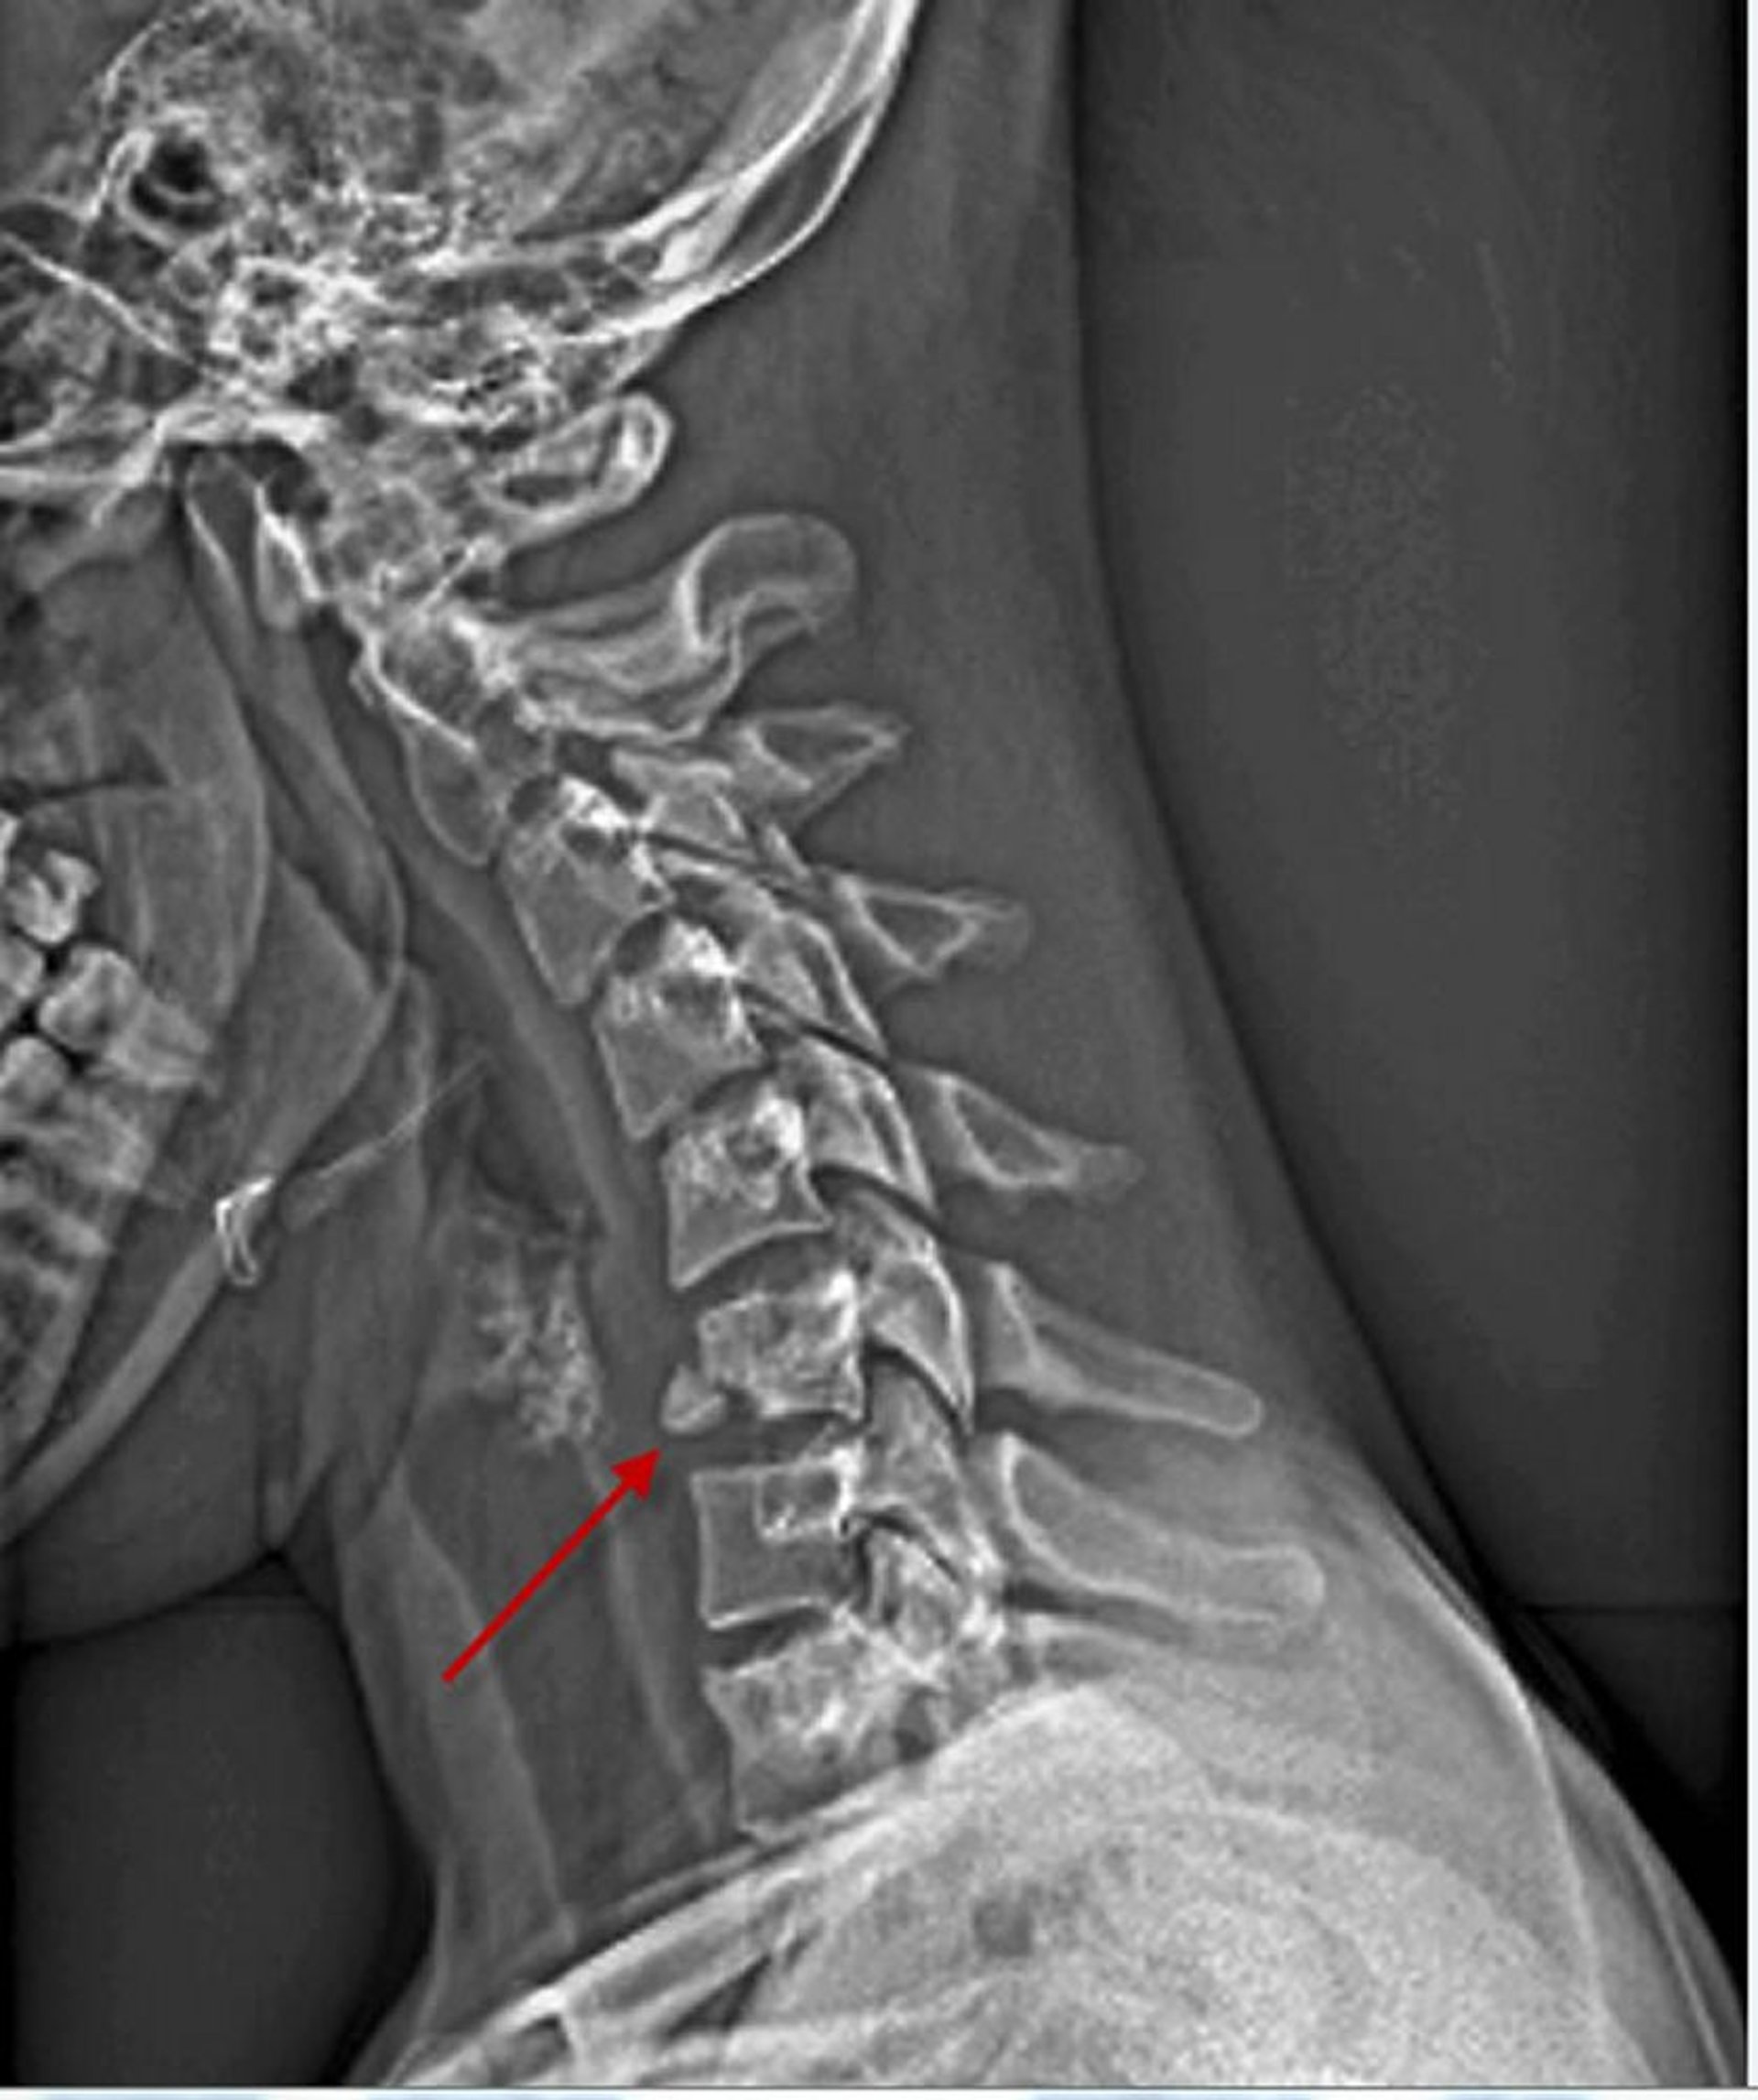

Fractura del cuerpo vertebral cervical

Esta vista lateral de la columna cervical muestra una fractura de la cara inferior anterior del sexto cuerpo vertebral (flecha).